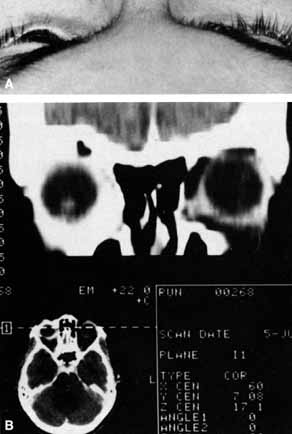

Ophthalmoscopy can be very helpful in orbital diagnosis. Optic disc edema may be caused either by papilledema (increased intracranial pressure) (Fig. 11A), papillitis (anterior optic neuritis) (Fig. 11B), or vasculitis (e.g., lupus erythematosus, sarcoidosis, Wegener's granulomatosis, and giant cell arteritis) (Fig. 11C).12 Papilledema (Fig. 11A) is usually present with near-normal visual function, although some patients may lose vision.9 In contrast, papillitis (Fig. 11B) characteristically leads to reduced visual function, commonly is associated with orbital pain, and is associated with inflammatory cells in the vitreous overlying the disc. Optic disc vasculitis (Fig. 11C) may be present with other findings of vasculitis, and commonly is associated with poor acuity and evidence of vascular occlusion (e.g., cotton-wool spots, hemorrhages). The differential diagnosis of the swollen, erythematous disc is discussed elsewhere in these volumes.

Fig. 11 A. Papilledema caused by pseudotumor cerebri. Visual acuity is 20/15 and the visual field is normal. B. Papillitis of anterior optic neuritis. Visual acuity is 20/400 with a relative afferent pupillary defect and a central scotoma. C. Vasculitis of optic disc caused by lupus erythematosus. Visual acuity is 20/200, there is a relative afferent pupillary defect, and a cecocentral scotoma. Note cotton-wool spots.

Optociliary shunts (Fig. 12A) develop as a result of long-term obstruction of the central retinal vein. This may occur secondary to optic nerve meningiomas,13 optic nerve gliomas,14,15 optic nerve meningoceles,16 central retinal vein occlusions,17 optic nerve sarcoidosis,18 craniosynostosis,19 optic nerve arachnoid cysts,20 optic disc drusen,21 and papilledema.15 Congenital optociliary shunts, which are exceedingly rare, have not been associated with optic neuropathy or orbital disease.22,23 The presence of optic nerve pallor, poor acuity and optociliary shunts generally implies an optic nerve meningioma in the absence of other funduscopic findings (Fig. 12B).13

Fig. 12 A. Optociliary shunt vessels (arrow) are present on the surface of an atrophic optic disc. The patient's visual acuity was hand motions. The patient demonstrates 2 mm of proptosis. B. Gadolinium-enhanced, fat-suppressed magnetic resonance imaging (MRI) demonstrates an intraorbital optic nerve sheath meningioma (arrow).